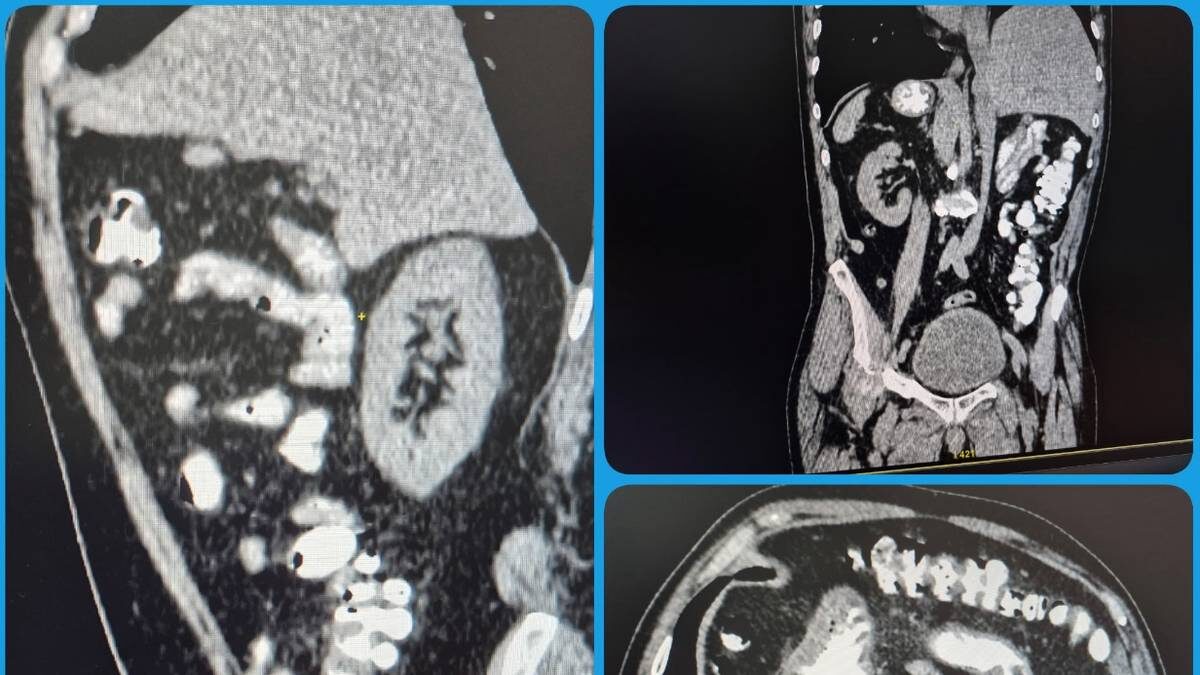

Житель Саратовской области в ходе КТ узнал о необычной анатомической особенности своего тела — все внутренние органы оказались расположены зеркально. Об этом рассказали в пресс-службе Балаковской городской клинической больницы. По словам представителей медучреждения, такая аномалия встречается довольно редко и является признаком «случайной находки» при обследовании. При этом сам пациент тоже удивился, узнав о своей особенности, так как до этого о ней даже не догадывался. — Отмечена полная транспозиция органов. На самочувствии пациента это никак не отражается, ни на что не влияет, — передает официальная страница больницы в VK. Другой случай произошел в Северной Ирландии, где местный житель Коннор Маккан случайно узнал о смертельной болезни после аварии. По его словам, он помнит, как дополз до тротуара, почувствовав, что не может управлять мышцами шеи, а затем потерял сознание. Тия Касл рассказала, что в молодости из-за редкой болезни у нее начались проблемы с мочеиспусканием, которые пр

Фото: пресс-служба Балаковской городской клинической больницы

Житель Саратовской области в ходе КТ узнал о необычной анатомической особенности своего тела — все внутренние органы оказались расположены зеркально. Об этом рассказали в пресс-службе Балаковской городской клинической больницы.

По словам представителей медучреждения, такая аномалия встречается довольно редко и является признаком «случайной находки» при обследовании. При этом сам пациент тоже удивился, узнав о своей особенности, так как до этого о ней даже не догадывался.

— Отмечена полная транспозиция органов. На самочувствии пациента это никак не отражается, ни на что не влияет, — передает официальная страница больницы в VK.